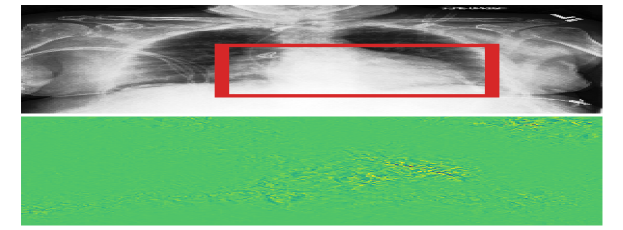

5.3 X-ray classification

As a real-world experiment, we study detection of pathologies in chest X-ray images. We use the ChestX-ray8 dataset Wang et al. (2017) as source domain and the CheXpert dataset Irvin et al. (2019) as target domain. As privileged information, we use bounding boxes localizing each pathology. For the CheXpert dataset, only pixel-level segmentations of pathologies are available, and we create bounding boxes that tightly enclose the segmentations. It is not obvious that the pixels within such a bounding box are sufficient for classifying the pathology, and we suspect that we may violate the assumptions of Proposition 1 in this experiment. However, as we find below, DALUPI-E2E improves empirical performance compared to baselines for small training sets, thereby demonstrating increased sample efficiency.

We consider the three pathologies that exist in both datasets and for which there are annotated findings: atelectasis (ATL; collapsed lung), cardiomegaly (CM; enlarged heart), and pleural effusion (PE; water around the lung). There are 457 and 118 annotated images in the source and target domain, respectively. We train DALUPI-E2E and DANN using all these images. SL-S is trained with the 457 source images and SL-T with the 118 target images as well as 339 labeled but non-annotated target images. Neither SL-S, SL-T nor DANN use any privileged information. In the annotated images, there are 180/146/153 and 75/66/64 examples of ATL/CM/PE in each domain respectively. Validation and test sets are sampled from the non-annotated images.

In Table 2 we present the per-class AUCs in the target domain. DALUPI-E2E outperforms all baseline models, including the target oracle, in detecting CM. For ATL and PE, it performs similarly to the other feasible models. That SL-T is better at predicting PE is not surprising given that this pathology is most prevalent in the target domain. In Figure 5(a), we show a single-finding image from the target test set with ground-truth label CM. The predicted bounding box of DALUPI-E2E with the highest probability is added to the image. DALUPI-E2E identifies the region of interest and makes a correct classification. The bottom panel shows the saliency map for the ground truth class for SL-S. We see that the gradients are mostly constant, indicating that the model is uncertain. In Figure 5(b), we show AUC for CM for DALUPI-E2E, SL-S, and SL-T trained with additional examples without bounding box annotations. We see that SL-S catches up to the performance of DALUPI-E2E when a large amount of labeled examples are provided. These results indicate that identifiability is not the primary obstacle for adaptation, and that PI improves sample efficiency.